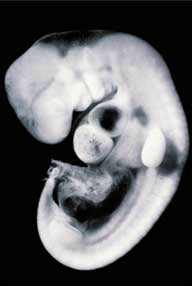

Can you identify this embryo? It's a human, photographed about 28 days after fertilization.